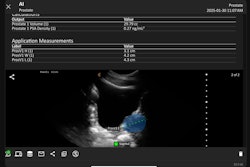

Clarius Bladder AI measures bladder volume and provides real-time feedback to clinicians. It recently received 510(k) clearance from the FDA. Image courtesy of PR Newswire.

The tool is now available in the U.S. with the Clarius PAL HD3, Clarius PA HD3, and the Clarius C3 HD3 wireless handheld ultrasound scanners. It provides real-time feedback to clinicians, with the company highlighting its uses in monitoring urinary retention and assessing bladder emptying in patients with neurogenic bladder or urinary tract obstruction.